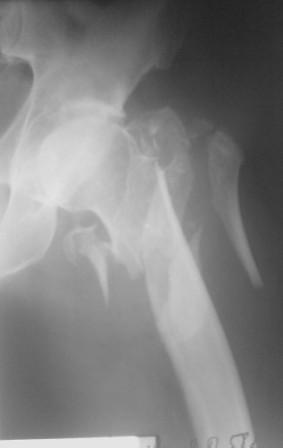

По нашему мнению линия перелома проходит вверху через латеральный отдел шейки бедра, вертельная область состоит из нескольких фрагментов. В таких условиях применить DHS или дистальную бедренную пластину LCP представляется нам сомнительным. Закрытый остеосинтез проксимальным гамма-гвоздем или PFNa невозможен т.к. нет ЭОПа.

Возможно открытый остеосинтез гвоздем PFNa?

Прилагаю Р-ы на вытяжении.